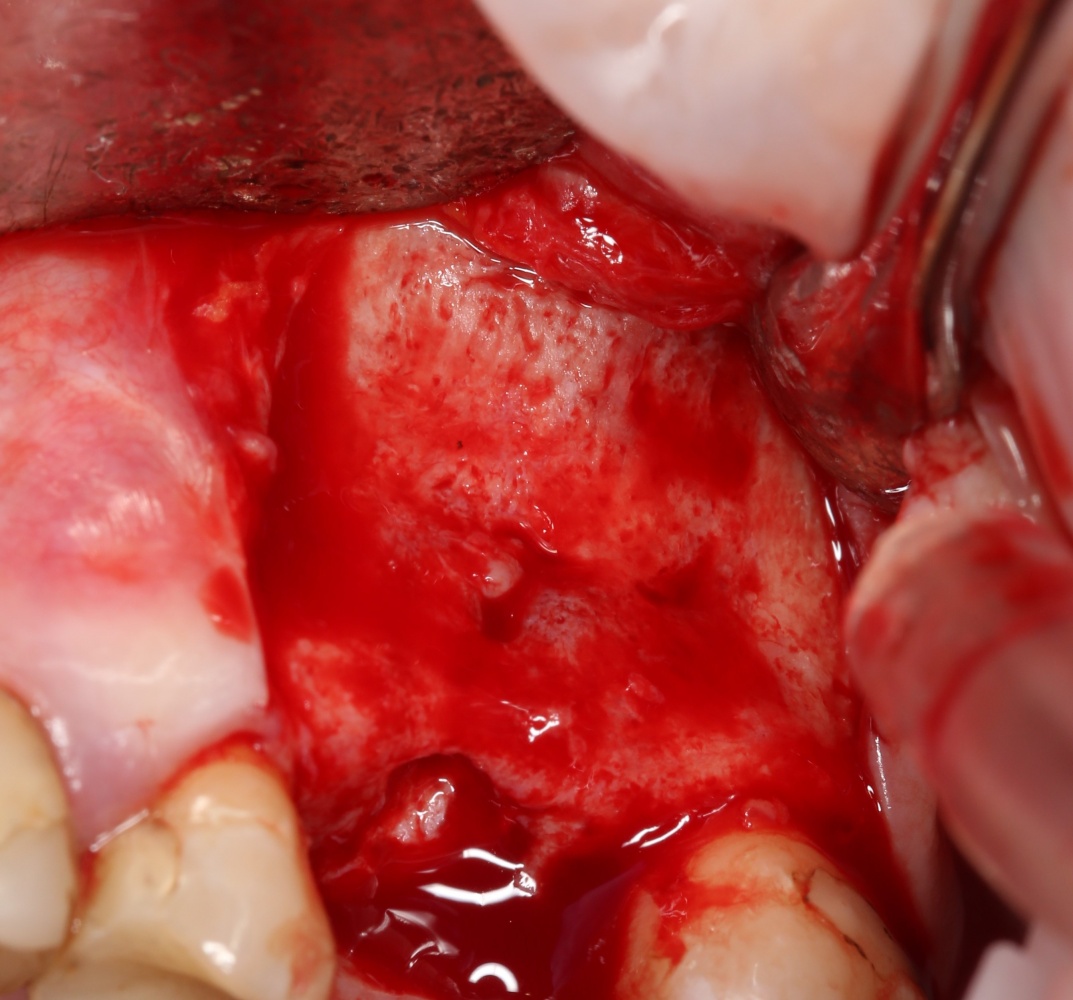

Вот клиническая картина через 4 месяца после ранее проведенной имплантации с остеопластикой:

Как видишь, коллеги из недалекой дружественной страны не осилили снятие швов. Мне это не нравится, хотя и объясняет, почему люди готовы ехать за тыщи километров ради 20-минутной операции удаления зуба мудрости.

Ну хорошо. Швы сняли. Делаем разрез. Обрати внимание, что после всех проведенных операций у нас остается очень небольшой по ширине слой жевательной слизистой оболочки: